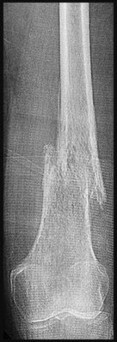

A 72-year-old female on prolonged bisphosphonate therapy presents with thigh pain.

Radiographs show a fracture of the femoral shaft. Which of the following radiographic features is most characteristic of an atypical femur fracture associated with bisphosphonate use?

Explanation

Atypical femur fractures (AFFs) associated with prolonged bisphosphonate therapy have specific major criteria defined by the ASBMR. These include a location anywhere from just distal to the lesser trochanter to just proximal to the supracondylar flare, transverse or short oblique orientation, non-comminuted (or minimally comminuted), and originating at the lateral cortex with localized periosteal or endosteal thickening ('beaking').